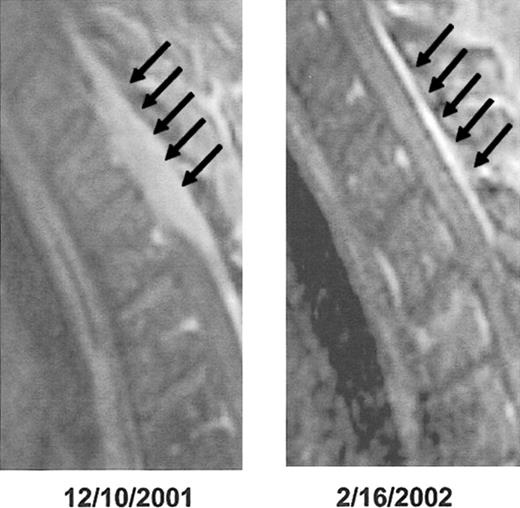

Local radiation, typically administered with high-dose dexamethasone, also has a palliative role for the treatment of focal lesions as part of disseminated myeloma. However, especially in patients with newly diagnosed disease, primary systemic therapy usually controls focal problems, including cord compression, as quickly and effectively as does local radiation (example, Figure 8). Avoiding radiation to major bone marrow–containing skeletal regions preserves the ability to procure adequate PBSC quantities. In advanced disease, it is critical to determine whether the source of pain is local tumor growth or vertebral collapse, with bone particles compressing the cord. In the latter case, surgical laminectomy is the preferred means of intervention. Vertebroplasty and kyphoplasty have both become important adjuncts of disease management, promptly alleviating pain because of vertebral collapse131,132 (example, Figure 9).

Cord compression detected by MRI. This is an example of rapid resolution of extensive spinal cord compression as a result of combination chemotherapy with DT PACE47 (dexamethasone 40 mg daily × 4, thalidomide 400 mg daily × 4, 4-day continuous intravenous infusions of cisplatin 10 mg/m2/d, Adriamycin 10 mg/m2/d, cyclophosphamide 400 mg/m2/d, and etoposide 40 mg/m2/d). Epidural disease from multiple myeloma responding to treatment: post-gadolinium T1-weighted MRI before (left) and after (right) treatment of epidural disease (arrows). Only a thin “stripe” of enhancing tissue remains after treatment.